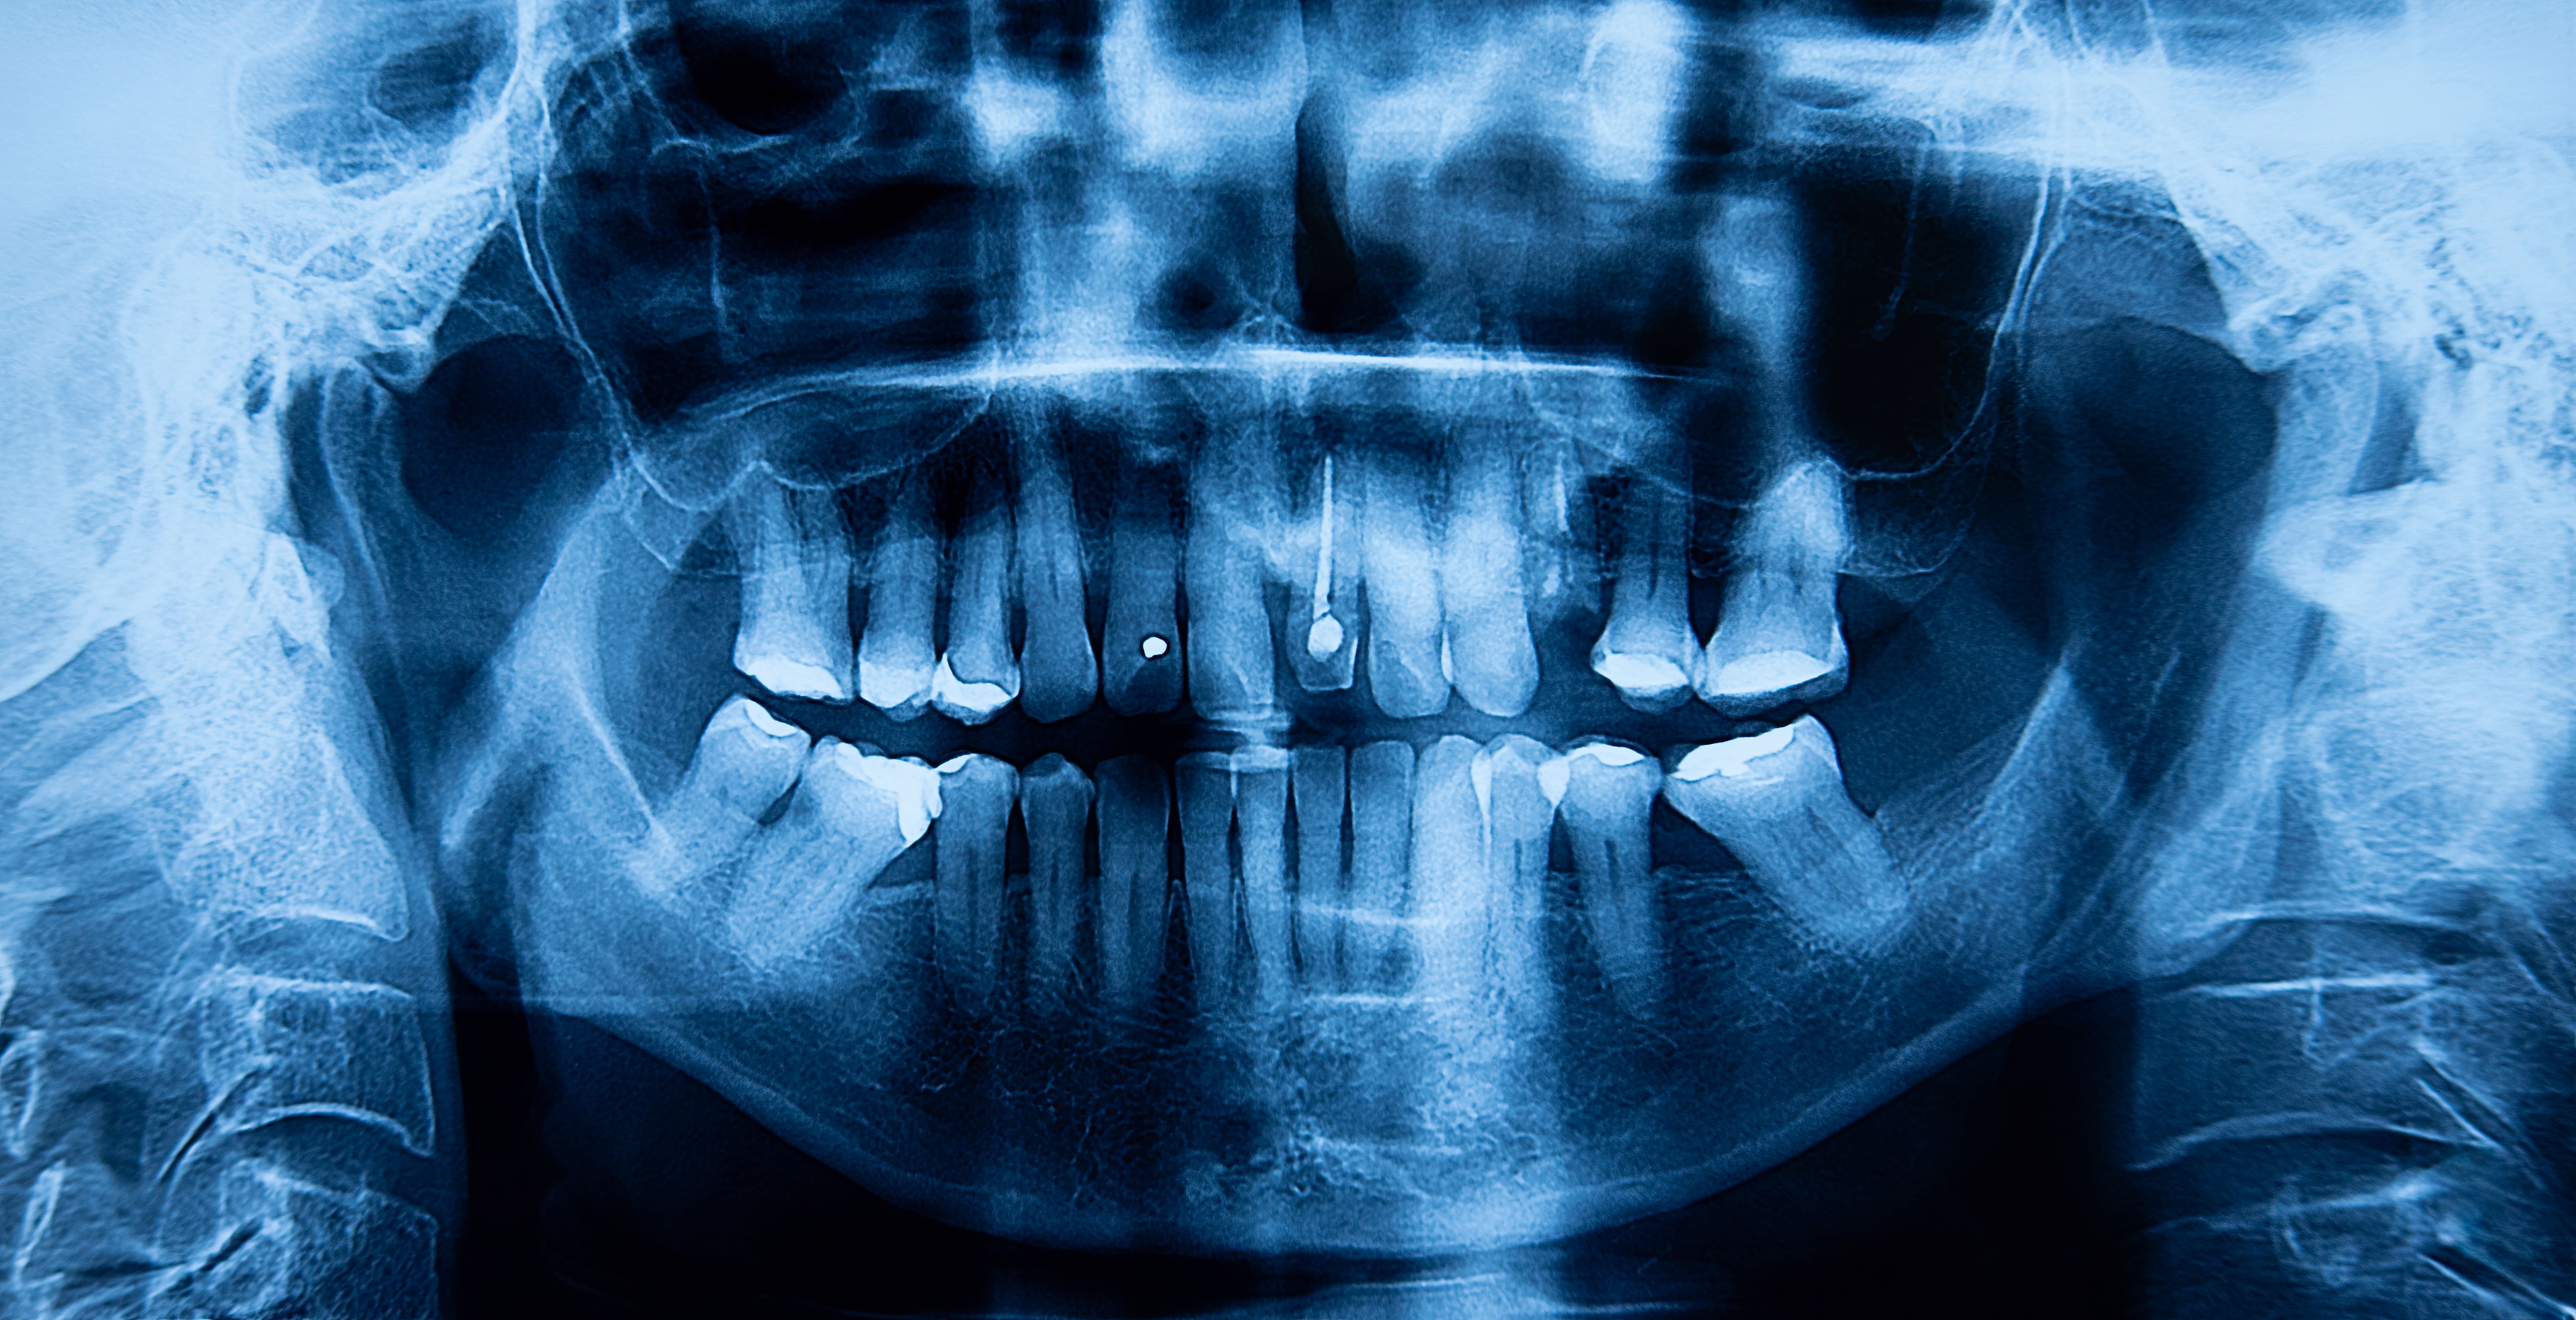

The root canal procedure typically involves several steps. First, the dentist will take an X-ray to determine the extent of the infection. Next, they will administer local anesthesia to numb the area. Then, a small hole is drilled into the tooth to access the pulp chamber. Using tiny instruments, the infected pulp is removed, and the inside of the tooth is cleaned and disinfected.